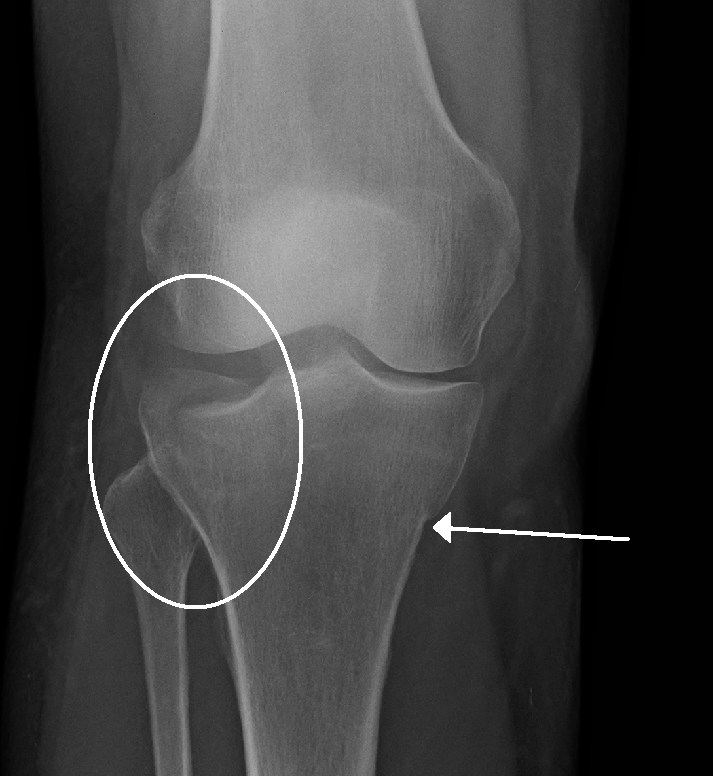

TIBIAL PLATEAU FRACTURE

The most common cause of a tibial plateau fracture is a valgus force with axial loading (force pushing outer knee inward). This commonly occurs in auto accidents when the flexed knee makes contact with the dashboard or in sports related injuries when the athlete lands from a jump and the knee “buckles”. At home or at work, people could fall from a height and attempt to land on their feet. While a fracture usually involves a high energy force, minimal or low intensity forces could lead to a fracture for an osteoporotic patient. In the event of a high energy incident the fracture site will most likely be a crack or split in the bone and with low energy incidents the bone is usually crushed.

- Type I: wedge or split fracture of the lateral condyle with no compression (depressed)

- Type II: wedge or split fracture of the lateral condyle with compression

- Type III: pure compression fracture of the lateral condyle

- Type IV: fracture that involves the medial condyle